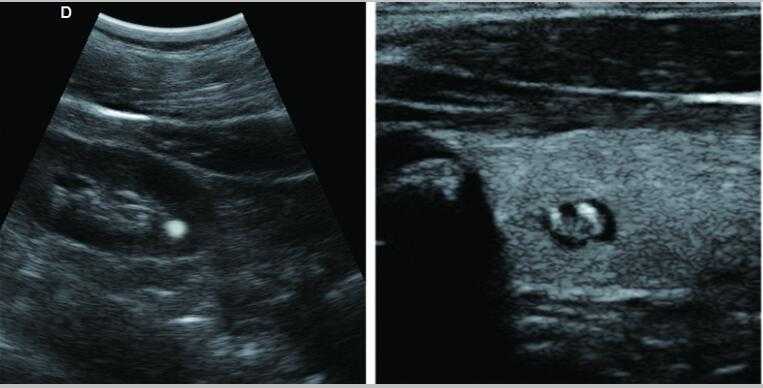

采用智能圖像處理技術1.組織諧波成像技術 2.噪聲抑制斑點技術 3.多波束并行處理技術等

7.應用:腹部、婦科、產科、心臟、血管和小器官、泌尿科、肌肉骨骼、兒科等